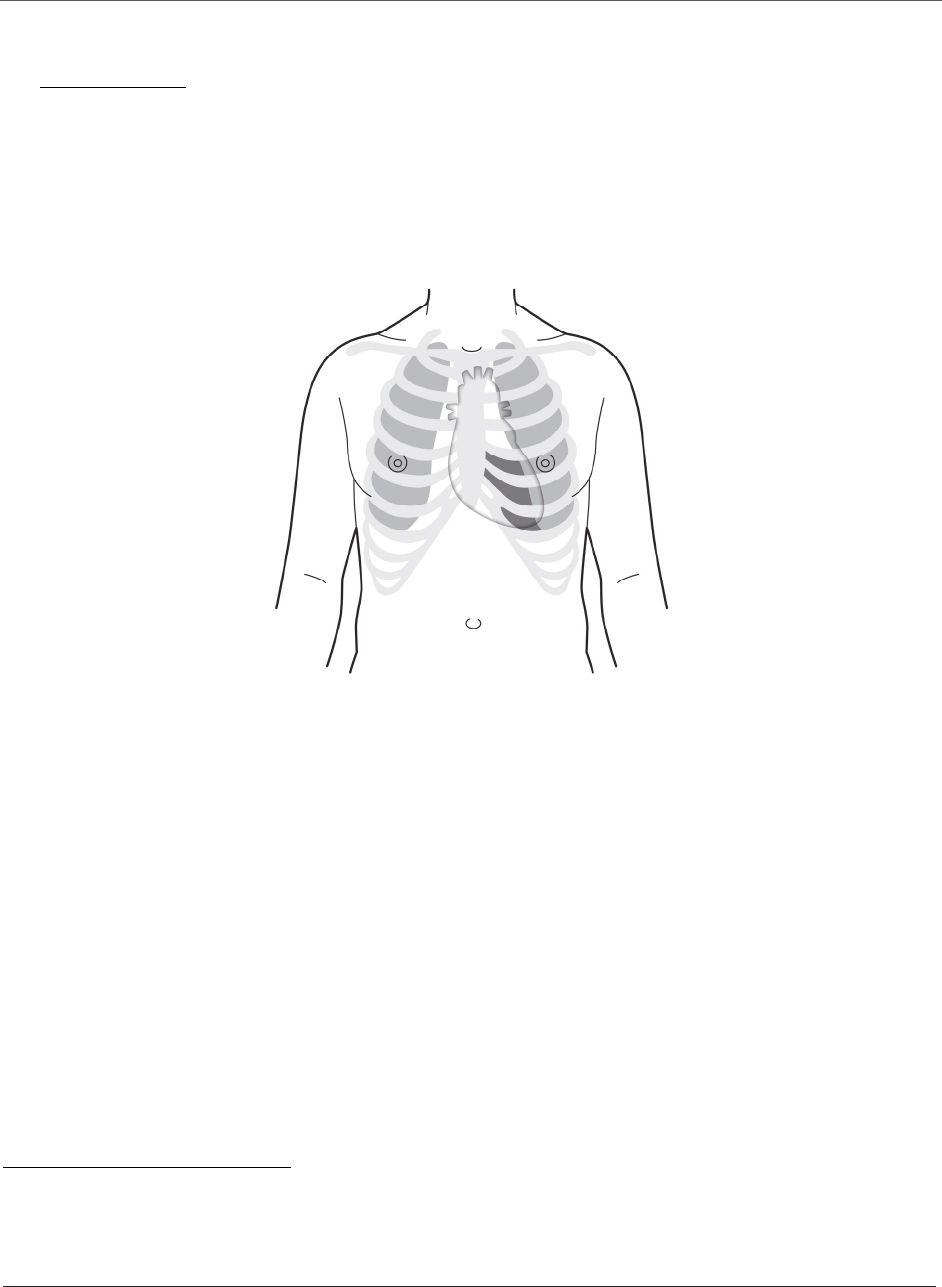

Figure1:TypicalacousticwindowoptionsforTransmitterimplant

ICS 4

ICS 5

ICS 6

ICS 7